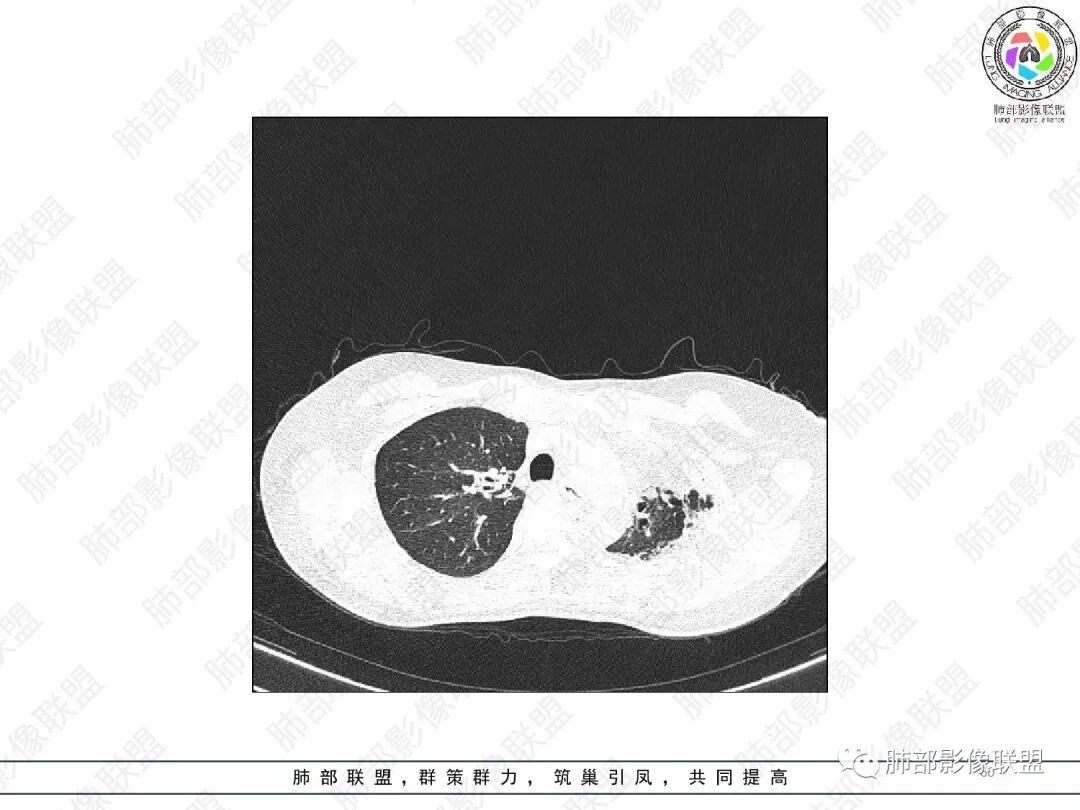

2.胸部CT:右肺上叶及中叶不规则块状影,沿支气管走行方向指套样影,支气阻塞湖嵌塞,腔内可见高密度影。灶周可见磨玻璃,外围见结节影及树芽征。左肺体积缩小,见不规则条索影、胸膜增厚,纵隔牵拉左移。

3.综合分析:结合患者病史及胸部CT主要鉴别ABPA(右肺上叶不规则块影,指套样顺延支气管方向,抗结核治疗1年,肺部病灶仍明显)及继发性肺结核TB(右肺上叶不规则肿块,其可见高密影,边缘模糊,周围卫星灶、树芽征,沿支气管爬行)。

完善气管镜及病理、检验结果(IgE显著增高)等支持ABPA诊断。且给予激素及伊曲康唑治疗后复查胸部CT提示病灶较前吸收,所以诊断明确。